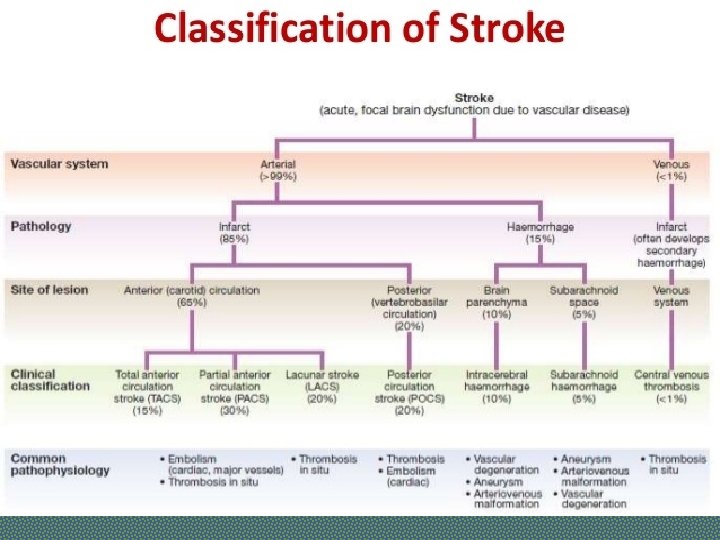

Stroke Ischaemic stroke/infarction (80%) Ø Thrombotic Ø Cardio-embolic Ø Large artery stenosis Ø Small vessel disease Ø Hypoperfusion Haemorrhagic stroke (17%) Ø Intracerebral hemorrhage (12%) Ø Subarachnoid hemorrhage (5%) Other (3%), e. g. arterial dissection, venous sinus thrombosis, vasculitis

Types of Stroke Depending upon the blood supply of affected area of brain, stroke can be of following types: § ANTERIOR CIRCULATION STROKE: Carotid system § POSTERIOR CIRCULATION STROKE: Vertebrobasilar system